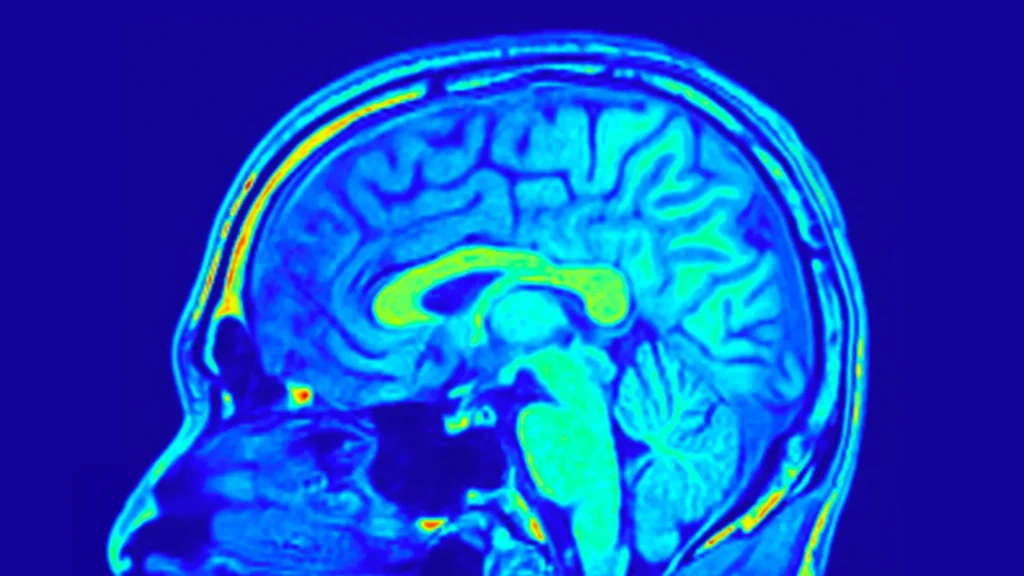

Para acompanhar os resultados, a equipe mediou a gravidade da depressão utilizando a Escala Hamilton de Depressão de 24 itens (HAMD-24), um questionário clínico amplamente utilizado. Eles também coletaram amostras de sangue periférico e realizaram ressonâncias magnéticas (RM) para examinar as mudanças na estrutura e na biologia cerebral.

Os dados de imagem cerebral revelaram insights ainda mais profundos. Os pesquisadores descobriram que redes específicas formadas por estruturas cerebrais podiam prever mudanças nos escores de depressão em ambos os grupos de tratamento. Essas redes refletem como diferentes regiões do cérebro estão organizadas e conectadas.

Mais surpreendentemente, certos padrões cerebrais eram preditivos apenas em pacientes que tomavam a Pílula Yueju. Esses padrões foram baseados na profundidade dos sulcos e na espessura cortical, que descrevem a dobra da superfície cerebral e a espessura da camada externa do cérebro. Ambas as características estão ligadas ao desenvolvimento e à função cerebral. Análises adicionais mostraram que a rede visual do cérebro desempenhava um papel particularmente importante na previsão de melhorias tanto nos sintomas de depressão quanto nos níveis de BDNF entre aqueles tratados com a Pílula Yueju.

Considerando todos os achados, as evidências sugerem que padrões de redes cerebrais identificados por meio de ressonâncias magnéticas poderiam ajudar a prever como pacientes individuais com TDM responderiam ao tratamento com a Pílula Yueju. Essa abordagem vai além da tomada de decisões baseada em sintomas e aponta para uma terapia antidepressiva mais personalizada.